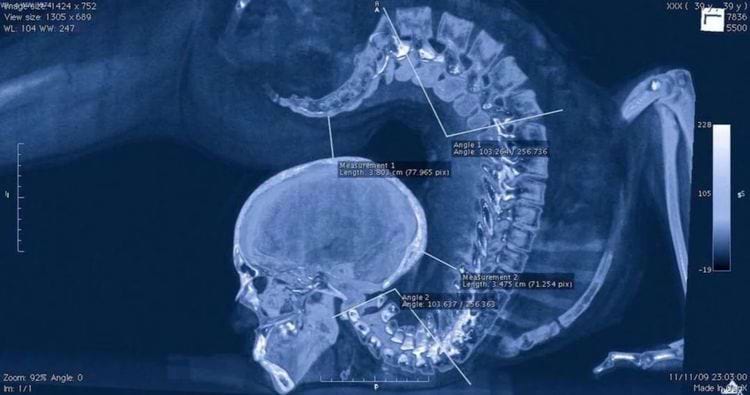

Рентгеновский снимок гимнастки, выполняющей упражнение